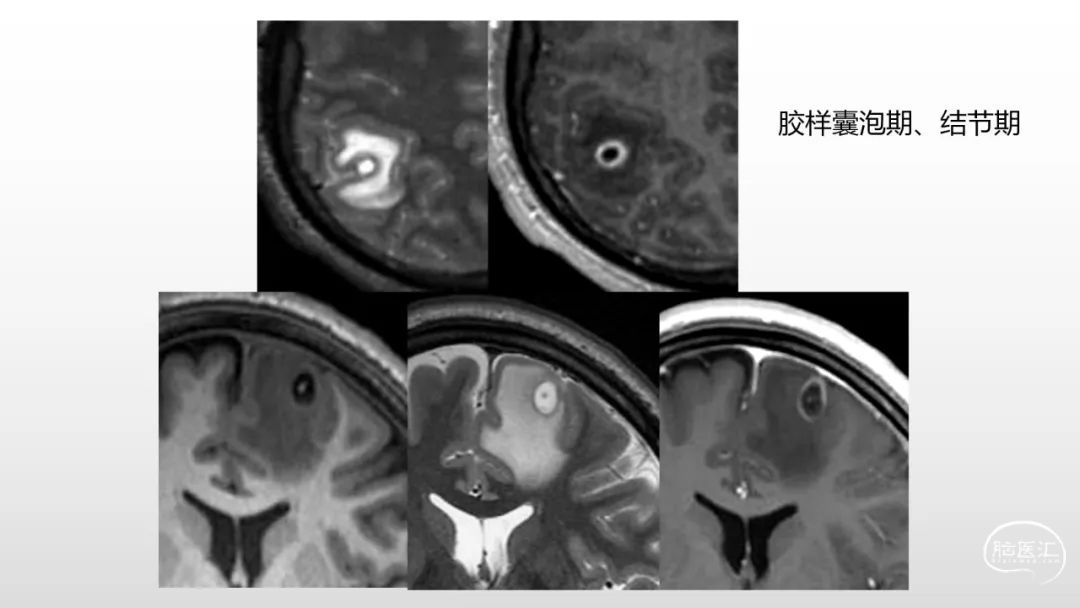

颅脑影像诊断基础知识讲座:感染和免疫性疾病1